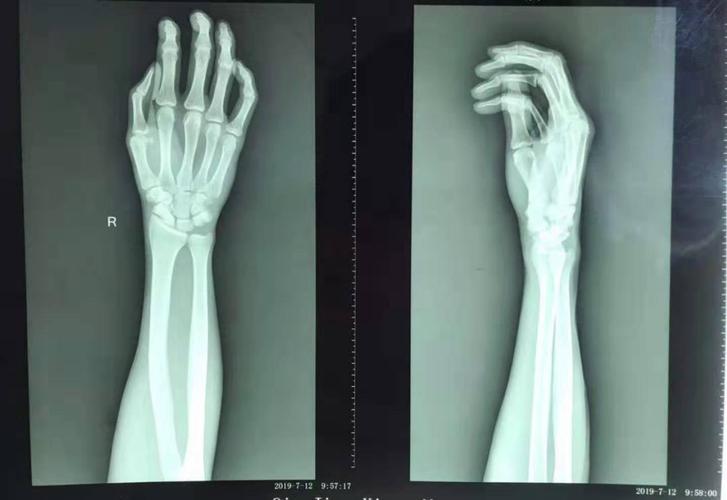

右手手腕骨裂图片,手腕骨折的真实图片

手腕骨折的真实图片

手腕骨裂

手腕骨断裂图片